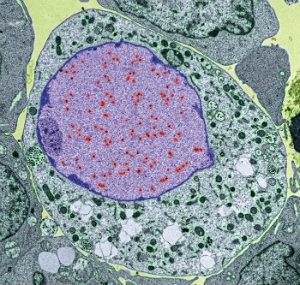

people worldwide, Epstein–Barr Virus (EBV) is a highly successful pathogen. We have co-evolved with this virus over millions of years, achieving a state of détente. EBV infection during childhood, which until recently was the normal state of affairs, usually passes unnoticed. Improvements in living standards mean that, increasingly, infection is delayed until adolescence or later, whereupon EBV infection can cause infectious mononucleosis (glandular fever) with symptoms of fever, sore throat, swollen lymph nodes and a debilitating fatigue that can persist for months. While most people mount a strong immune response able to control their EBV infection, the virus nevertheless establishes a lifelong infection of B cells hidden from the immune system. Periodically, the virus reactivates in some of these cells to complete its life cycle, producing new viruses that are spread to other people via saliva.